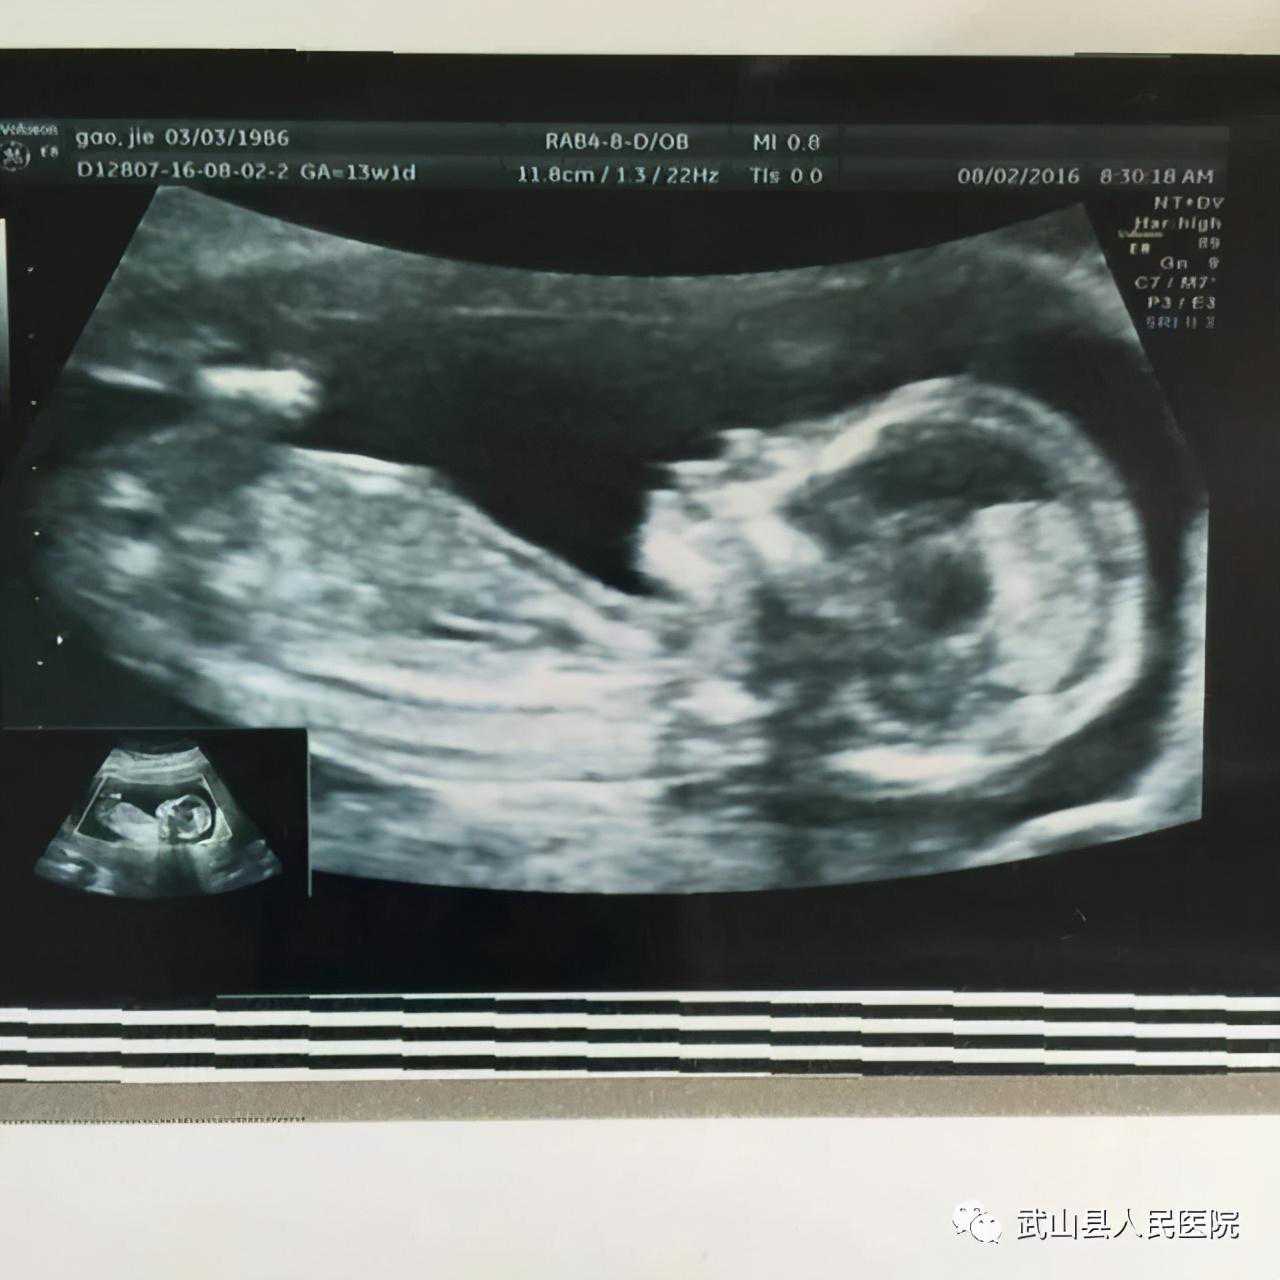

1.孕11周----13+6周胎儿NT检查

明确妊娠胎儿数目、羊膜囊及绒毛膜囊数目;生长参数测量评估胎儿大小;NT值(颈项透明层厚度)测量及鼻骨观察判断胎儿染色体异常风险;筛查胎儿颅脑、肢体等严重的结构异常。